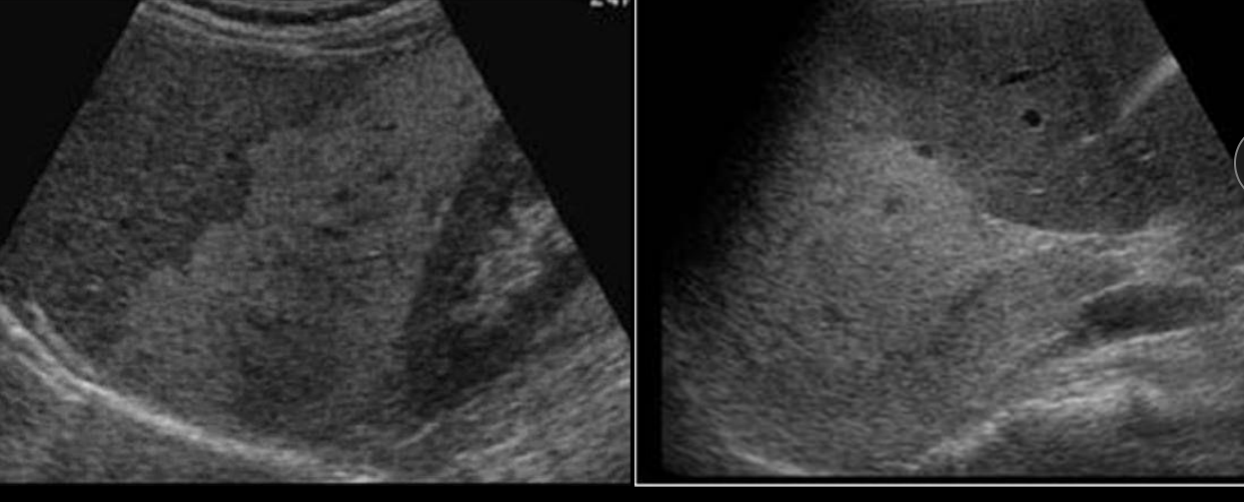

10

Q

A

Muy blanco y con textura gruesa en margenes

Cirrosis